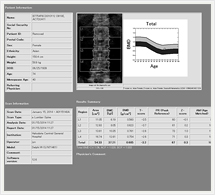

骨密度測定検査(DXA)

骨密度測定検査とは

体の中の腰椎等の骨密度を弱いX線を使用して非侵襲に測定し、骨粗鬆症の診断や、その経過観察に有用な情報をもたらす検査法です。

検査所要時間は10分程度で、検査による痛みはございませんので安心して検査をお受け下さい。

画像紹介